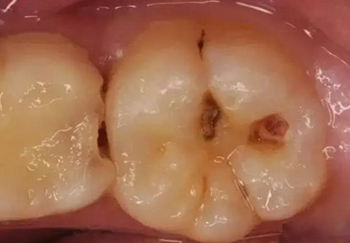

第三步:深齲

當(dāng)您進食時,沒法咬食物,您說:“還好,可以用另外一邊牙齒咬。”

牙醫(yī)告誡說:“病變已經(jīng)破壞到了牙本質(zhì)深層,牙齒有較深的齲洞,溫度刺激,化學(xué)刺激以及食物進入齲洞時均引起疼痛,此時,及時做充填治療的話還來得及保住牙髓。”